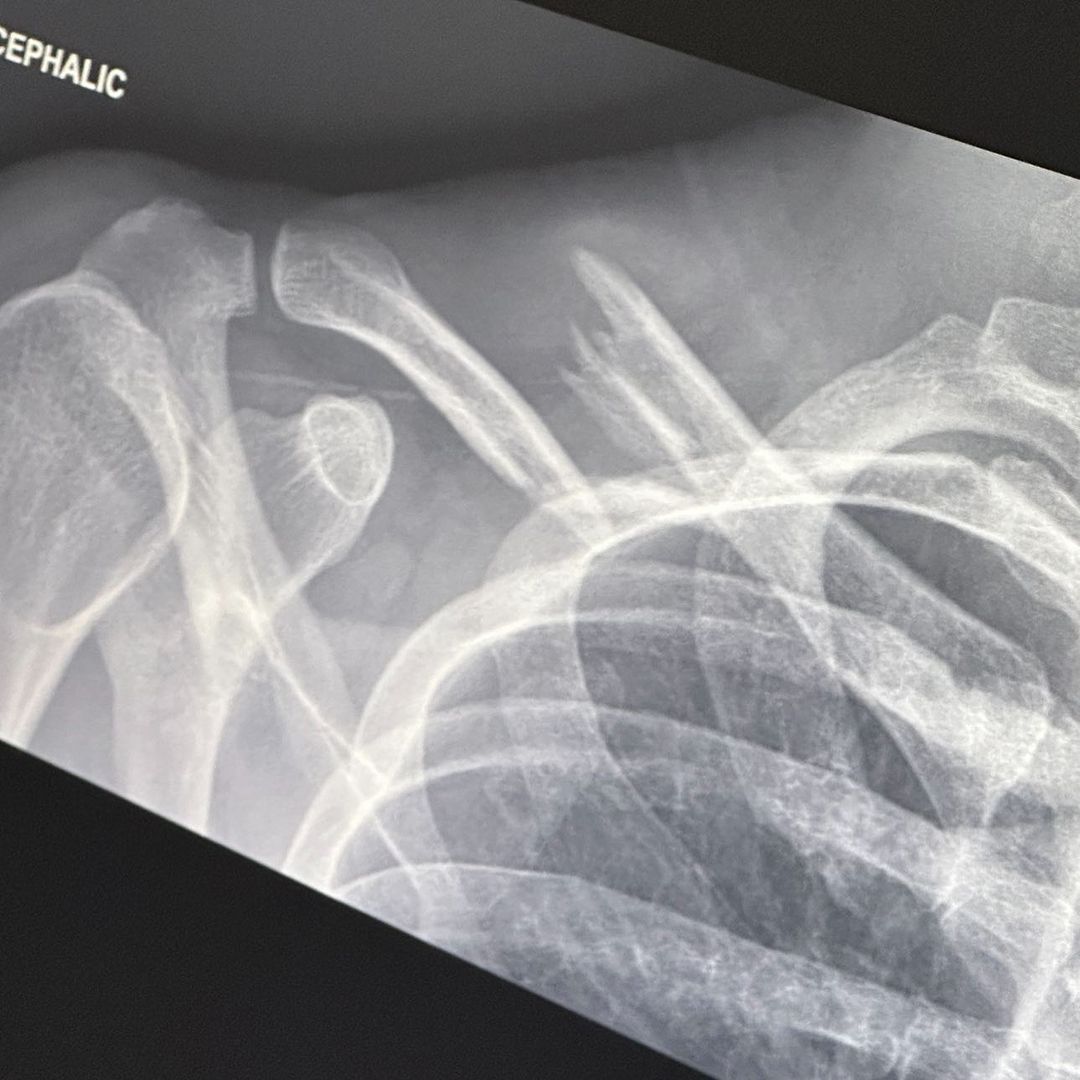

Last Friday, I had the pleasure of crashing my electric bike, flying over the handlebars and absolutely demolishing my collarbone as well as sustaining a radial head fracture to my right elbow. The severity of the displacement of my collarbone meant I required surgery which I am now on the other side of and I’m feeling great! I want to give an enormous thank you to Dr. Brian Lee who performed the surgery, Dr. Neal Elattrache and everyone at Kerlan Jobe for their incredible treatment I feel so privileged to have received. I’d also like to thank Jonathan Erb PT for guiding me through the treatment process as well as the ongoing process of physical rehab I now face. I also want to thank my family for their support and love, and most of all Claudia for dropping everything to take care of me the second this happened. She has been an Angel through all of this. I’m told with hard work, I’ll be able to play billie’s forum shows come December which I am so grateful for. As foolish as I felt after the fall, my prevailing emotion is gratitude. You see, I was not wearing a helmet. Lesson forever learned. I feel so lucky to still be here. Take care of yourselves, thank your bodies for all that they do for you. See you all again soon ♥️